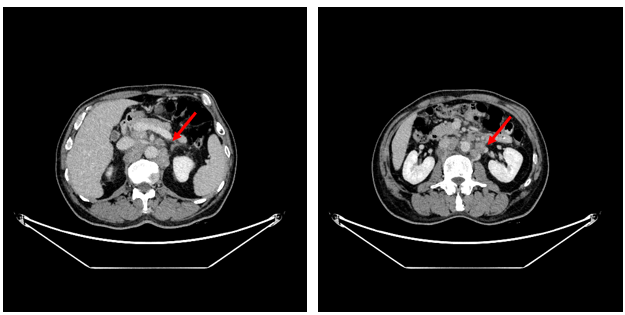

2022年6月2日全腹增强CT:胃癌并腹腔及腹膜后多发淋巴结转移;肝多发异常强化结节,考虑转移。

图2.全腹CT

从指南可以看出,HER2阳性胃癌是一类特殊的疾病亚型,需抗HER2治疗。并且免疫联合化疗目前在晚期胃癌或可考虑全人群推荐。该患者为HER2阳性胃癌伴腹腔淋巴结、腹膜后淋巴结、左锁骨上淋巴结、肺、肝多发转移。给予曲妥珠单抗靶向治疗+抗PD-1单抗免疫治疗+XELOX方案化疗4周期后取得了PR的状态,肺上的病灶几乎消失,转移淋巴结也有了非常明显的缩小。CA199从初治前的5413U/ml恢复到正常范围。

本例患者是1例晚期HER2阳性胃癌,伴有多处淋巴结、肺、肝转移,经过信迪利单抗+曲妥珠单抗(汉曲优)+XELOX方案化疗4周期后疗效评价达到PR,肺上的病灶几乎消失,转移淋巴结也有了非常明显的缩小。治疗过程中仅观察到胃肠道反应,心脏、肝肾功能毒性及免疫治疗相关毒性均未出现。证实了化疗联合汉曲优和抗PD-1单抗对晚期HER2阳性胃癌疗效和安全性。